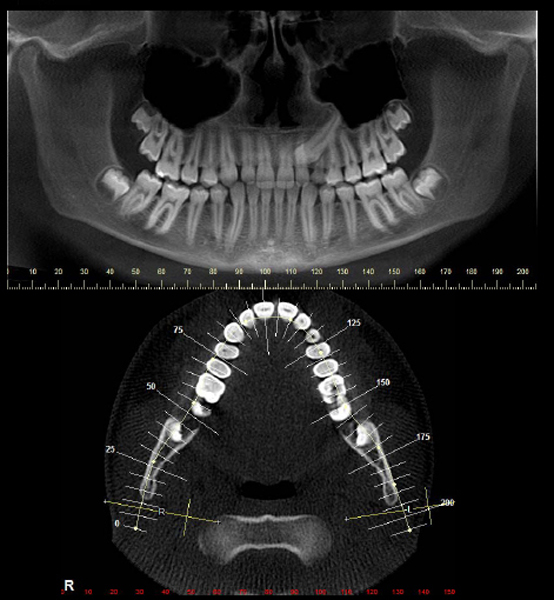

Radiografia Panorâmica

Documentações Ortodônticas

É um conjunto de exames (radiografias, fotografias , análises, modelos) que são imprescindíveis para que juntamente com a anamnese, exame clinico, exame funcional seja feito o diagnóstico e planejamento ortodôntico .Além disso, servem como um registro para comparação e avaliação dos resultados do tratamento ortodôntico e como documentação legal.